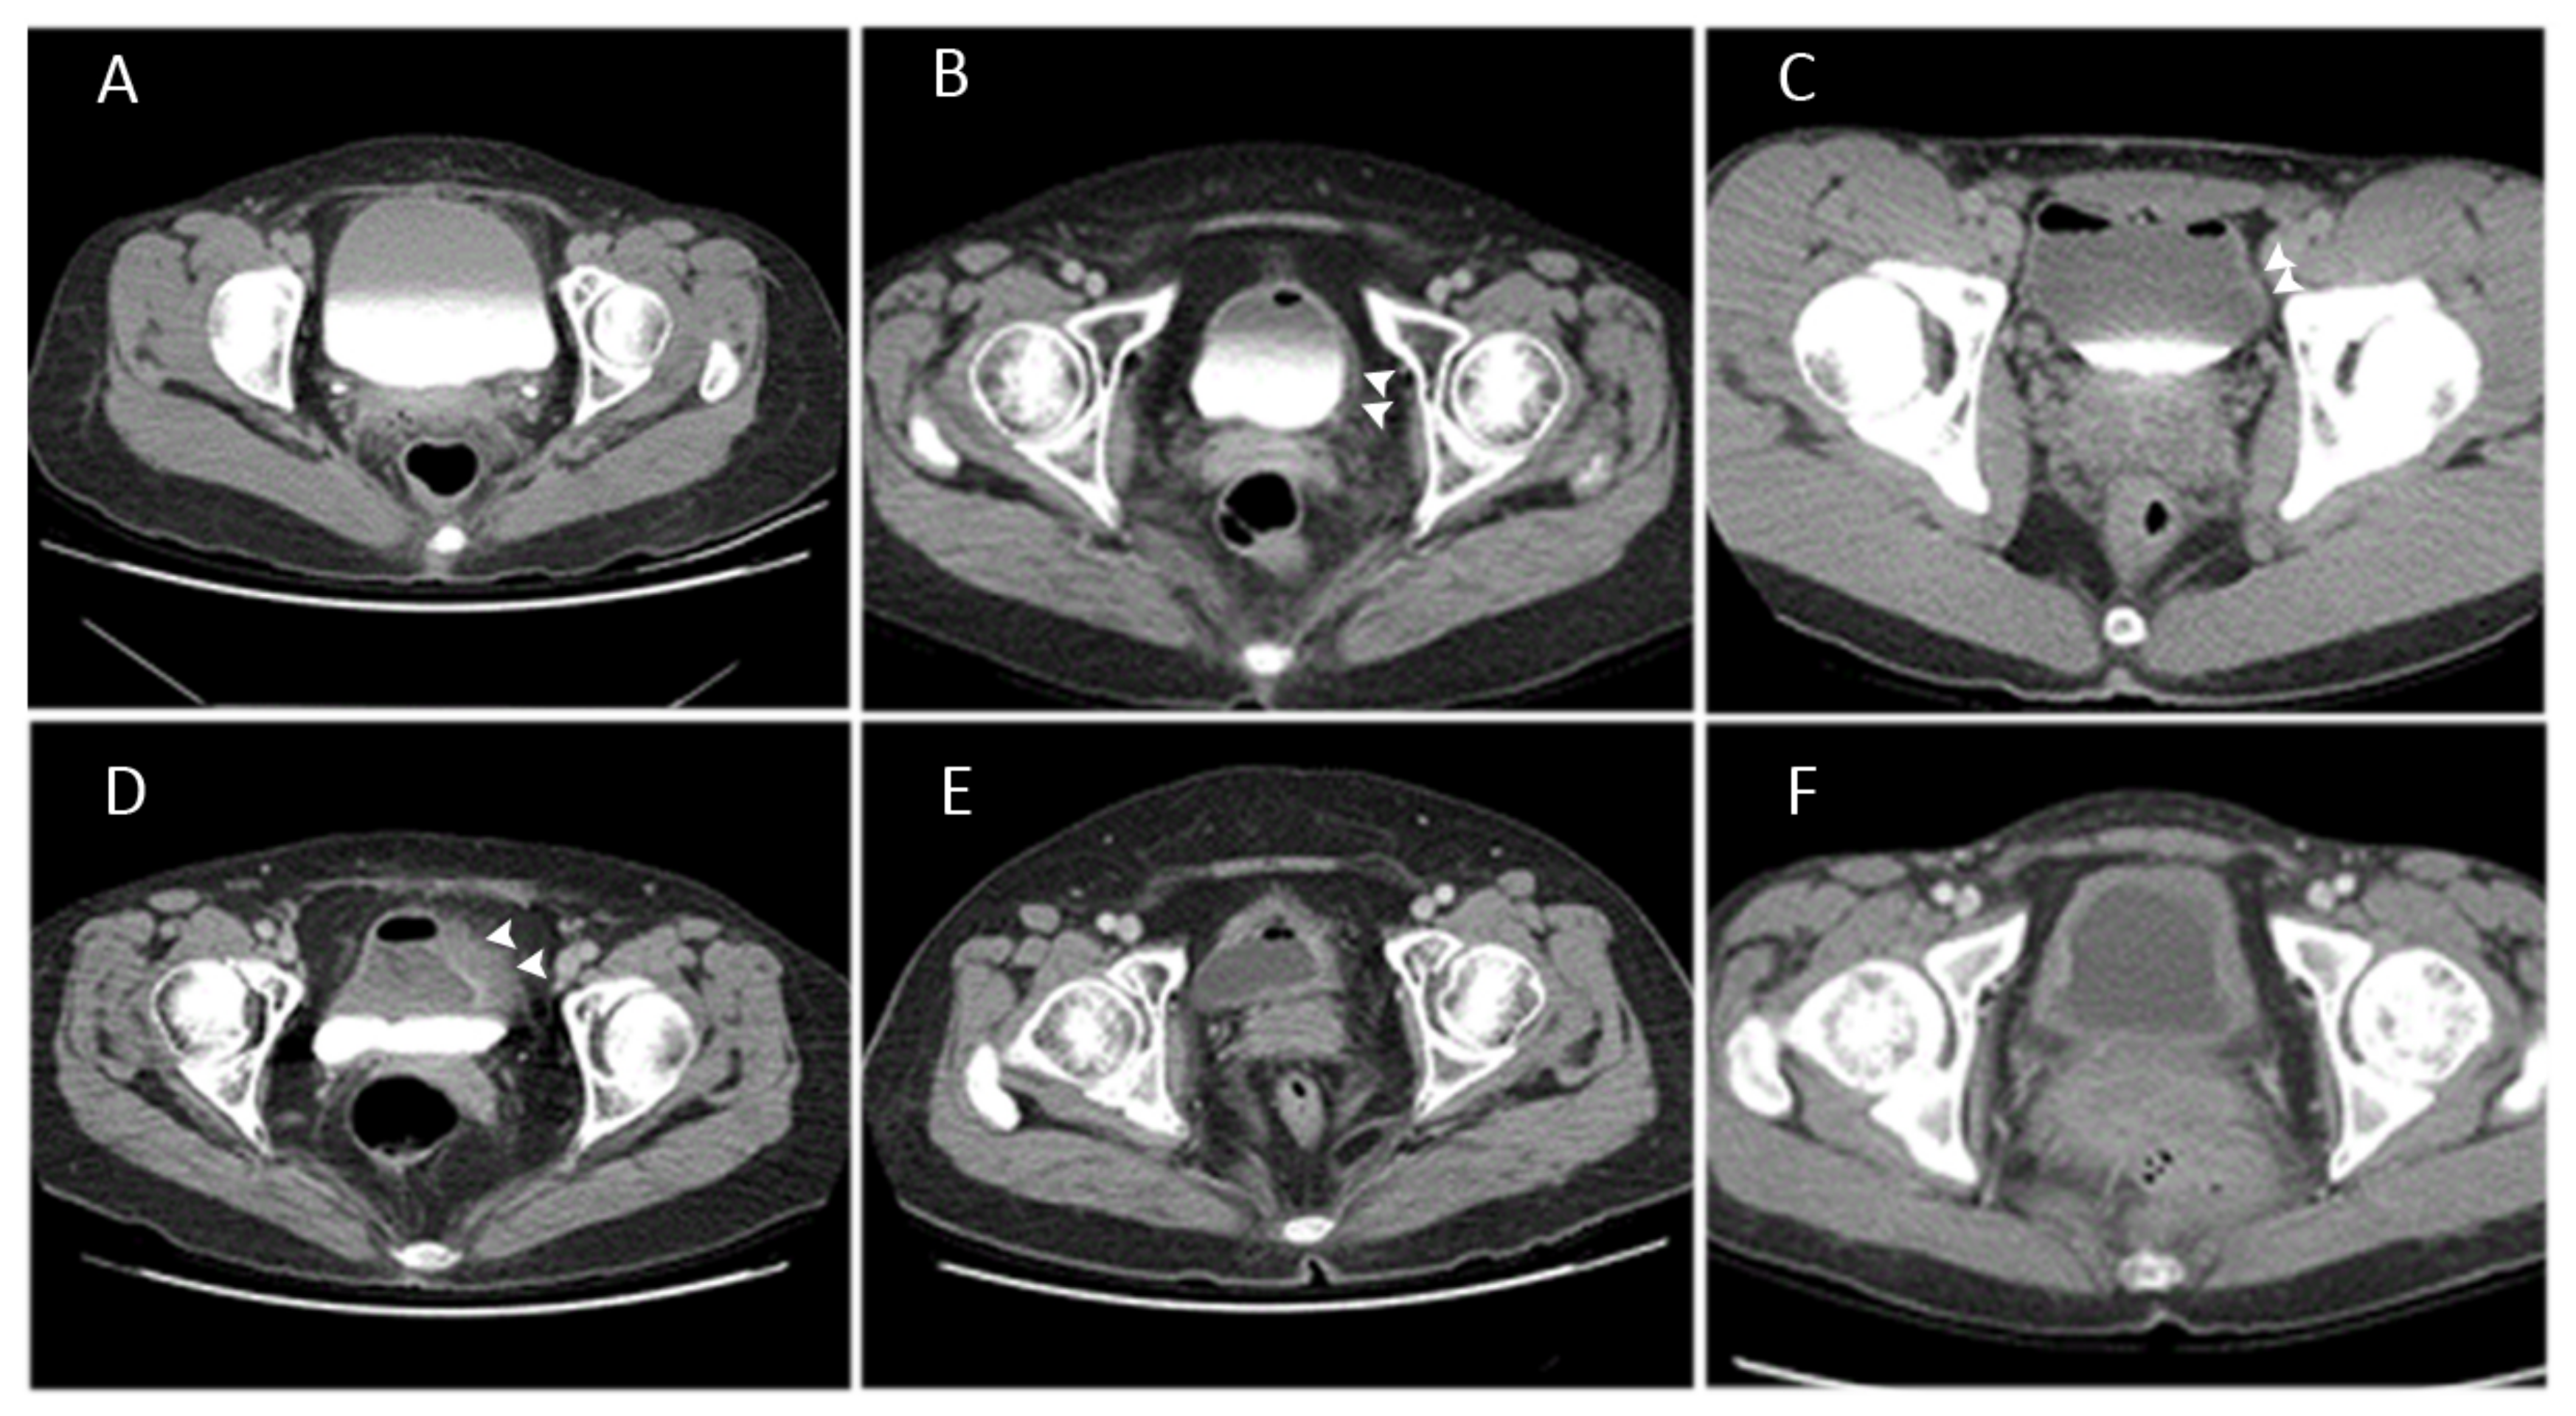

Possible Association between Bladder Wall Morphological Changes on Computed Tomography and Bladder-Centered Interstitial Cystitis/Bladder Pain Syndrome

3. Results